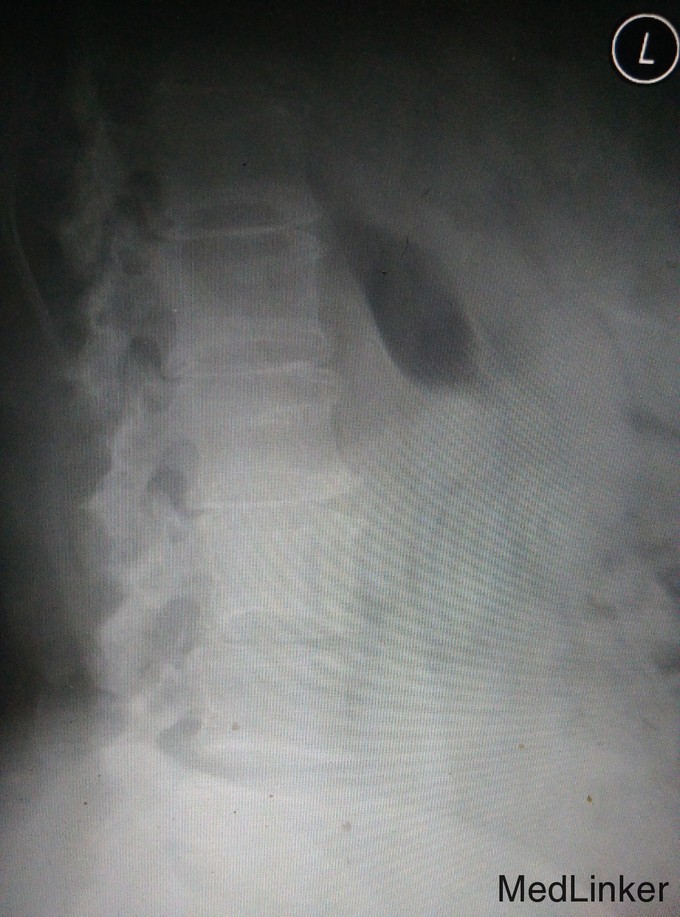

主诉:反复腰痛6年,加重伴双下肢麻木5个月。 病史:6年前无明显诱因出现反复发作腰部疼痛,无双下肢麻木及放射痛,劳累后加重,休息可缓解,5个月前出现上述症状加重,步行约300米后出现双下肢麻木乏力,休息后可继续行走,大小便正常。

查体:脊柱生理弯曲存在,无腰椎侧突畸形,腰4-骶1椎旁压痛和深部扣击痛(+),腰部活动稍受限,直腿抬高试验双侧阴性,双下肢浅感觉无明显减退,双下肢肌力4级,双下肢膝反射和踝反射稍减弱,髌阵挛、踝阵挛未引出。病理反射未引出,肛周浅感觉正常,肛门反射正常。 腰椎CT及腰椎MRI示:L4-5、L5-S1椎间盘突出,椎管狭窄,黄韧带肥厚,相应硬膜囊受压。